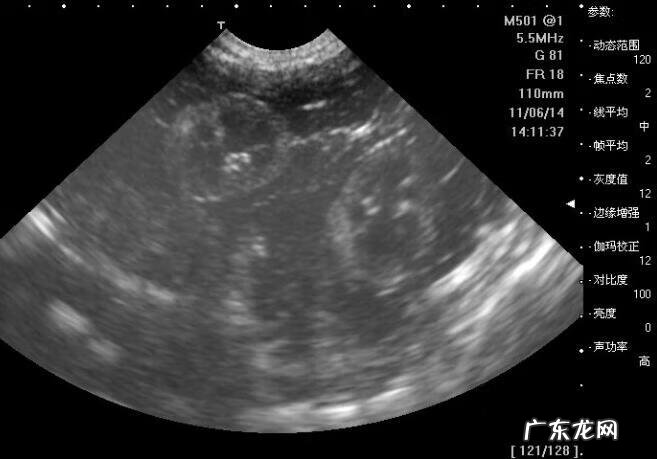

孕妇在怀孕的时候做十几次产前检查,B超一般都要做三五次,相信大家最熟悉不过了 。通过B超,可以看出宝宝的生长发育、有没有畸形、胎盘的位置等情况 。

可是各项数据好像天书,什么BPF、FL啊,真的很头疼,这些到底是什么意思,反映了什么情况呢?宝妈们一起来看看吧: